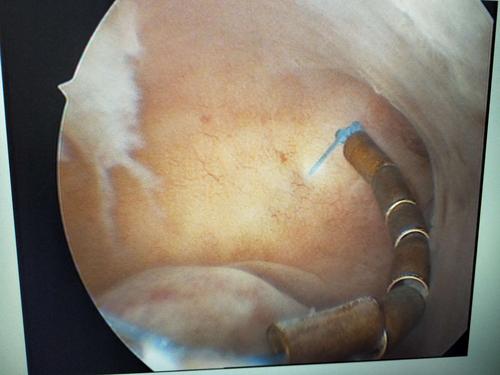

这是宫腔内节育环合并有内膜息肉.

宫腔镜直视下取环